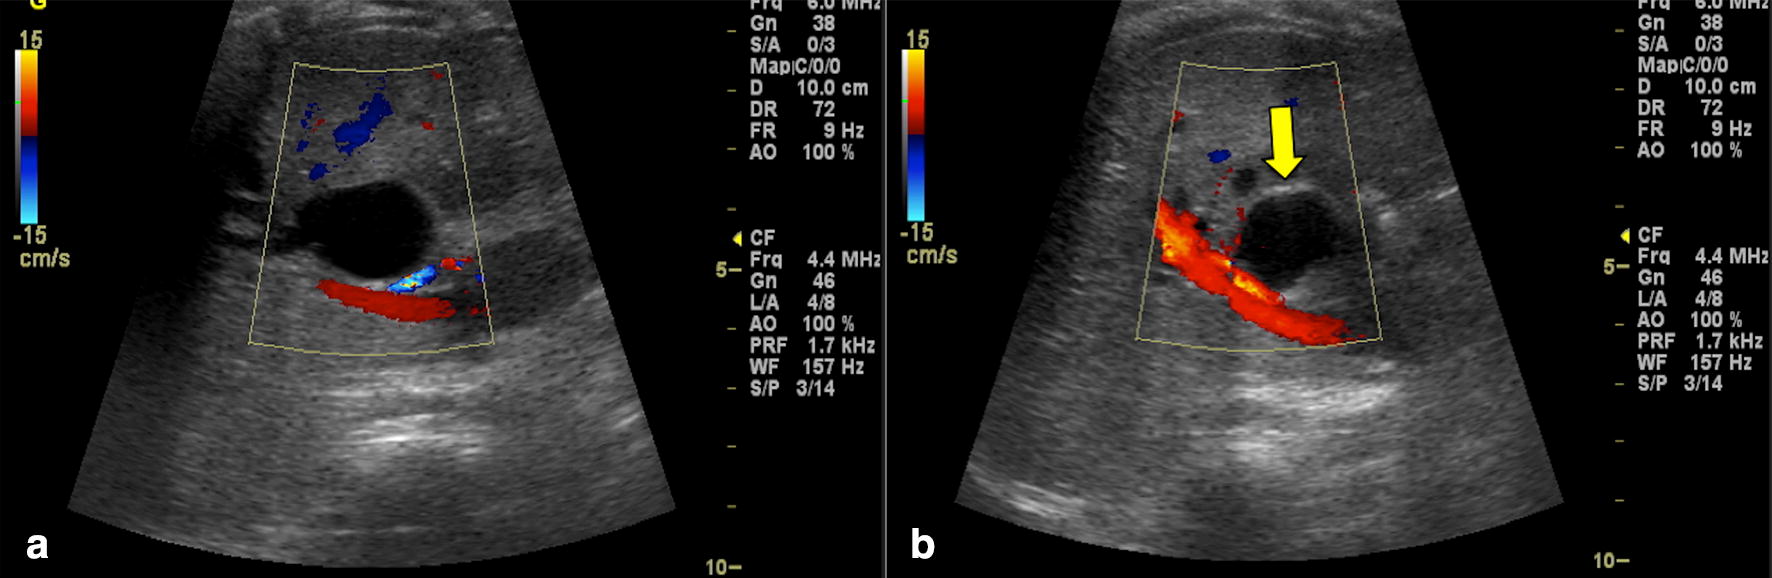

Ultrasound findings in paediatric cholestasis how to image the patient

Ultrasound findings in paediatric cholestasis how to image the patient Cholestasis Ultrasound Images cholestasis represents an impaired secretion of bilirubin by hepatocytes, manifesting with high blood levels of conjugated bilirubin and. imaging of the liver and biliary tract via abdominal ultrasound is important to detect. biliary atresia is a congenital biliary disorder that is characterized by an absence or severe deficiency of the. radiologic imaging is obtained in the. Cholestasis Ultrasound Images.